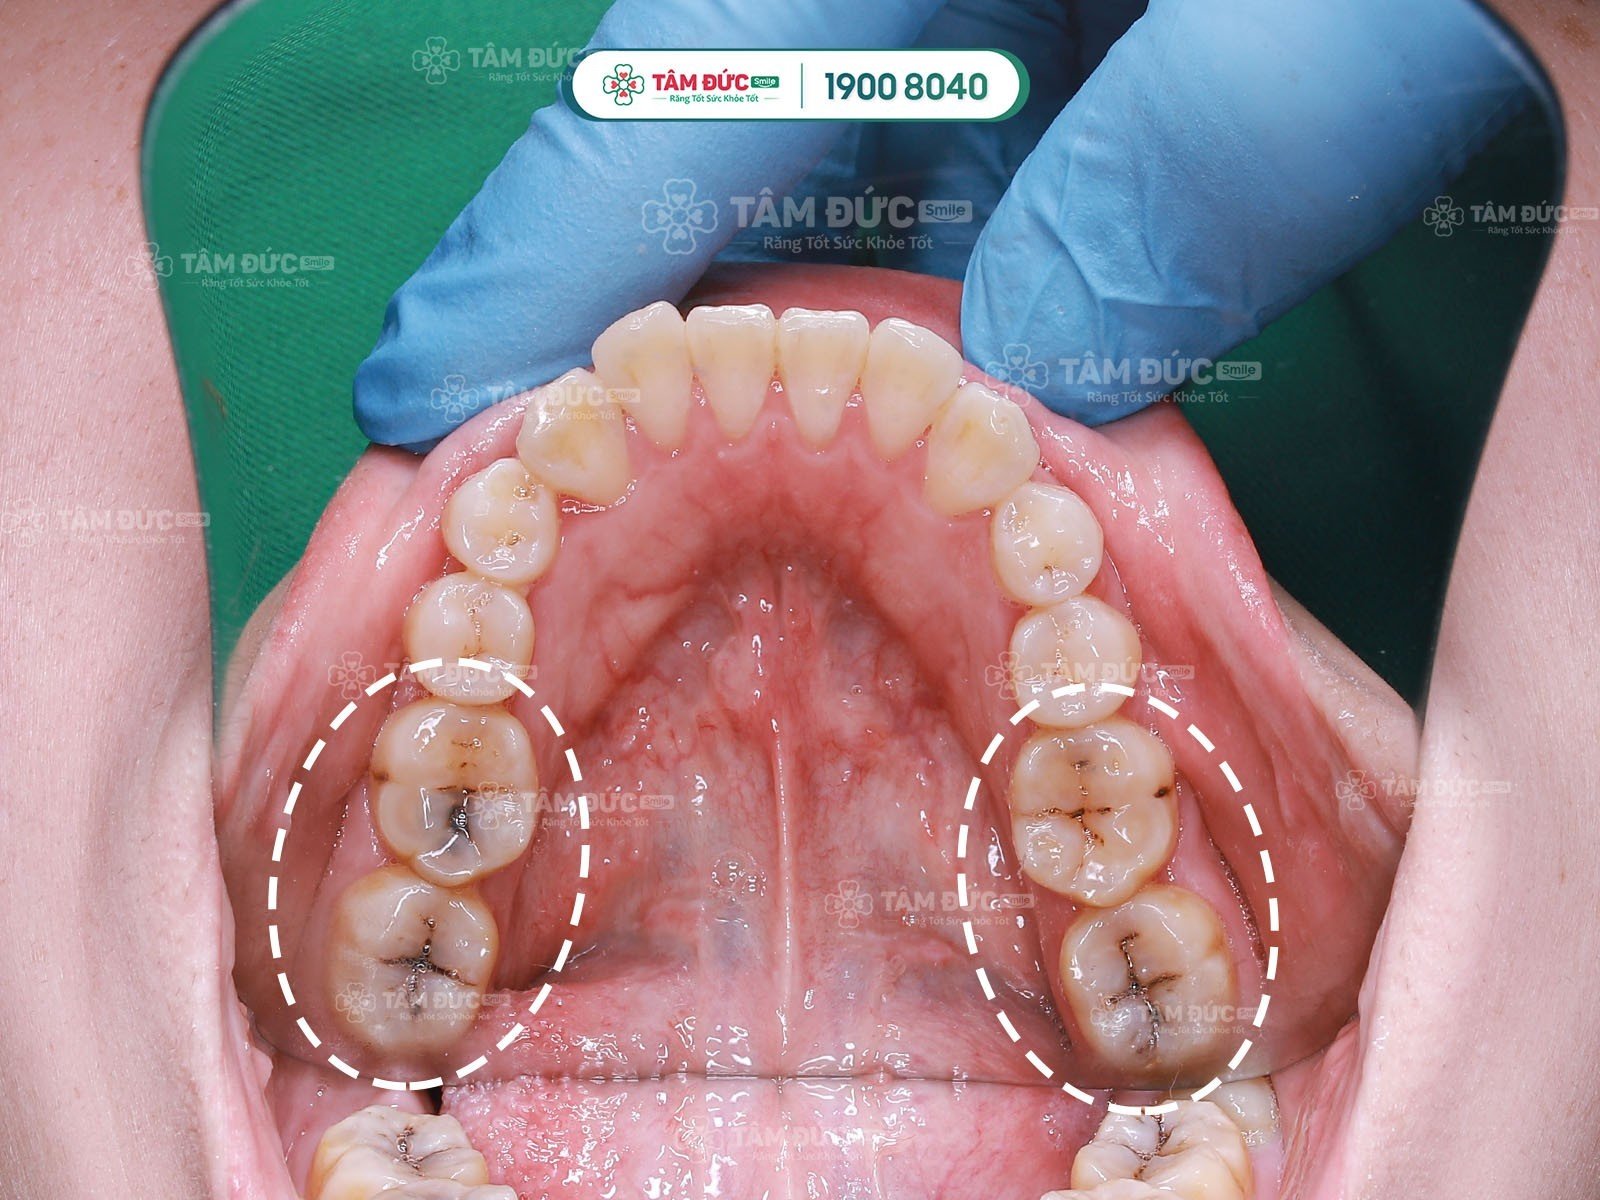

Pulpitis is a common dental condition that can cause significant pain and discomfort. It is often triggered by factors such as tooth decay, periodontitis, dental trauma, or frequent consumption of extremely hot or cold foods.

1. Cases Requiring Root Canal Treatment

1.1. Indications for Endodontic (Root Canal) Treatment